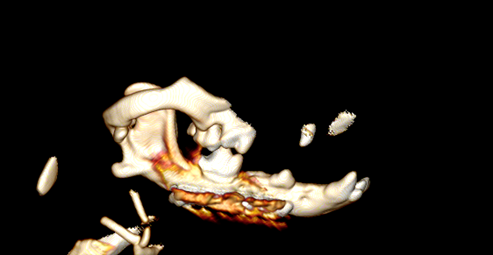

Postoperatieve CT-beelden na plaatfixatie met 1.5mm locking LCP plaat en dito schroeven.